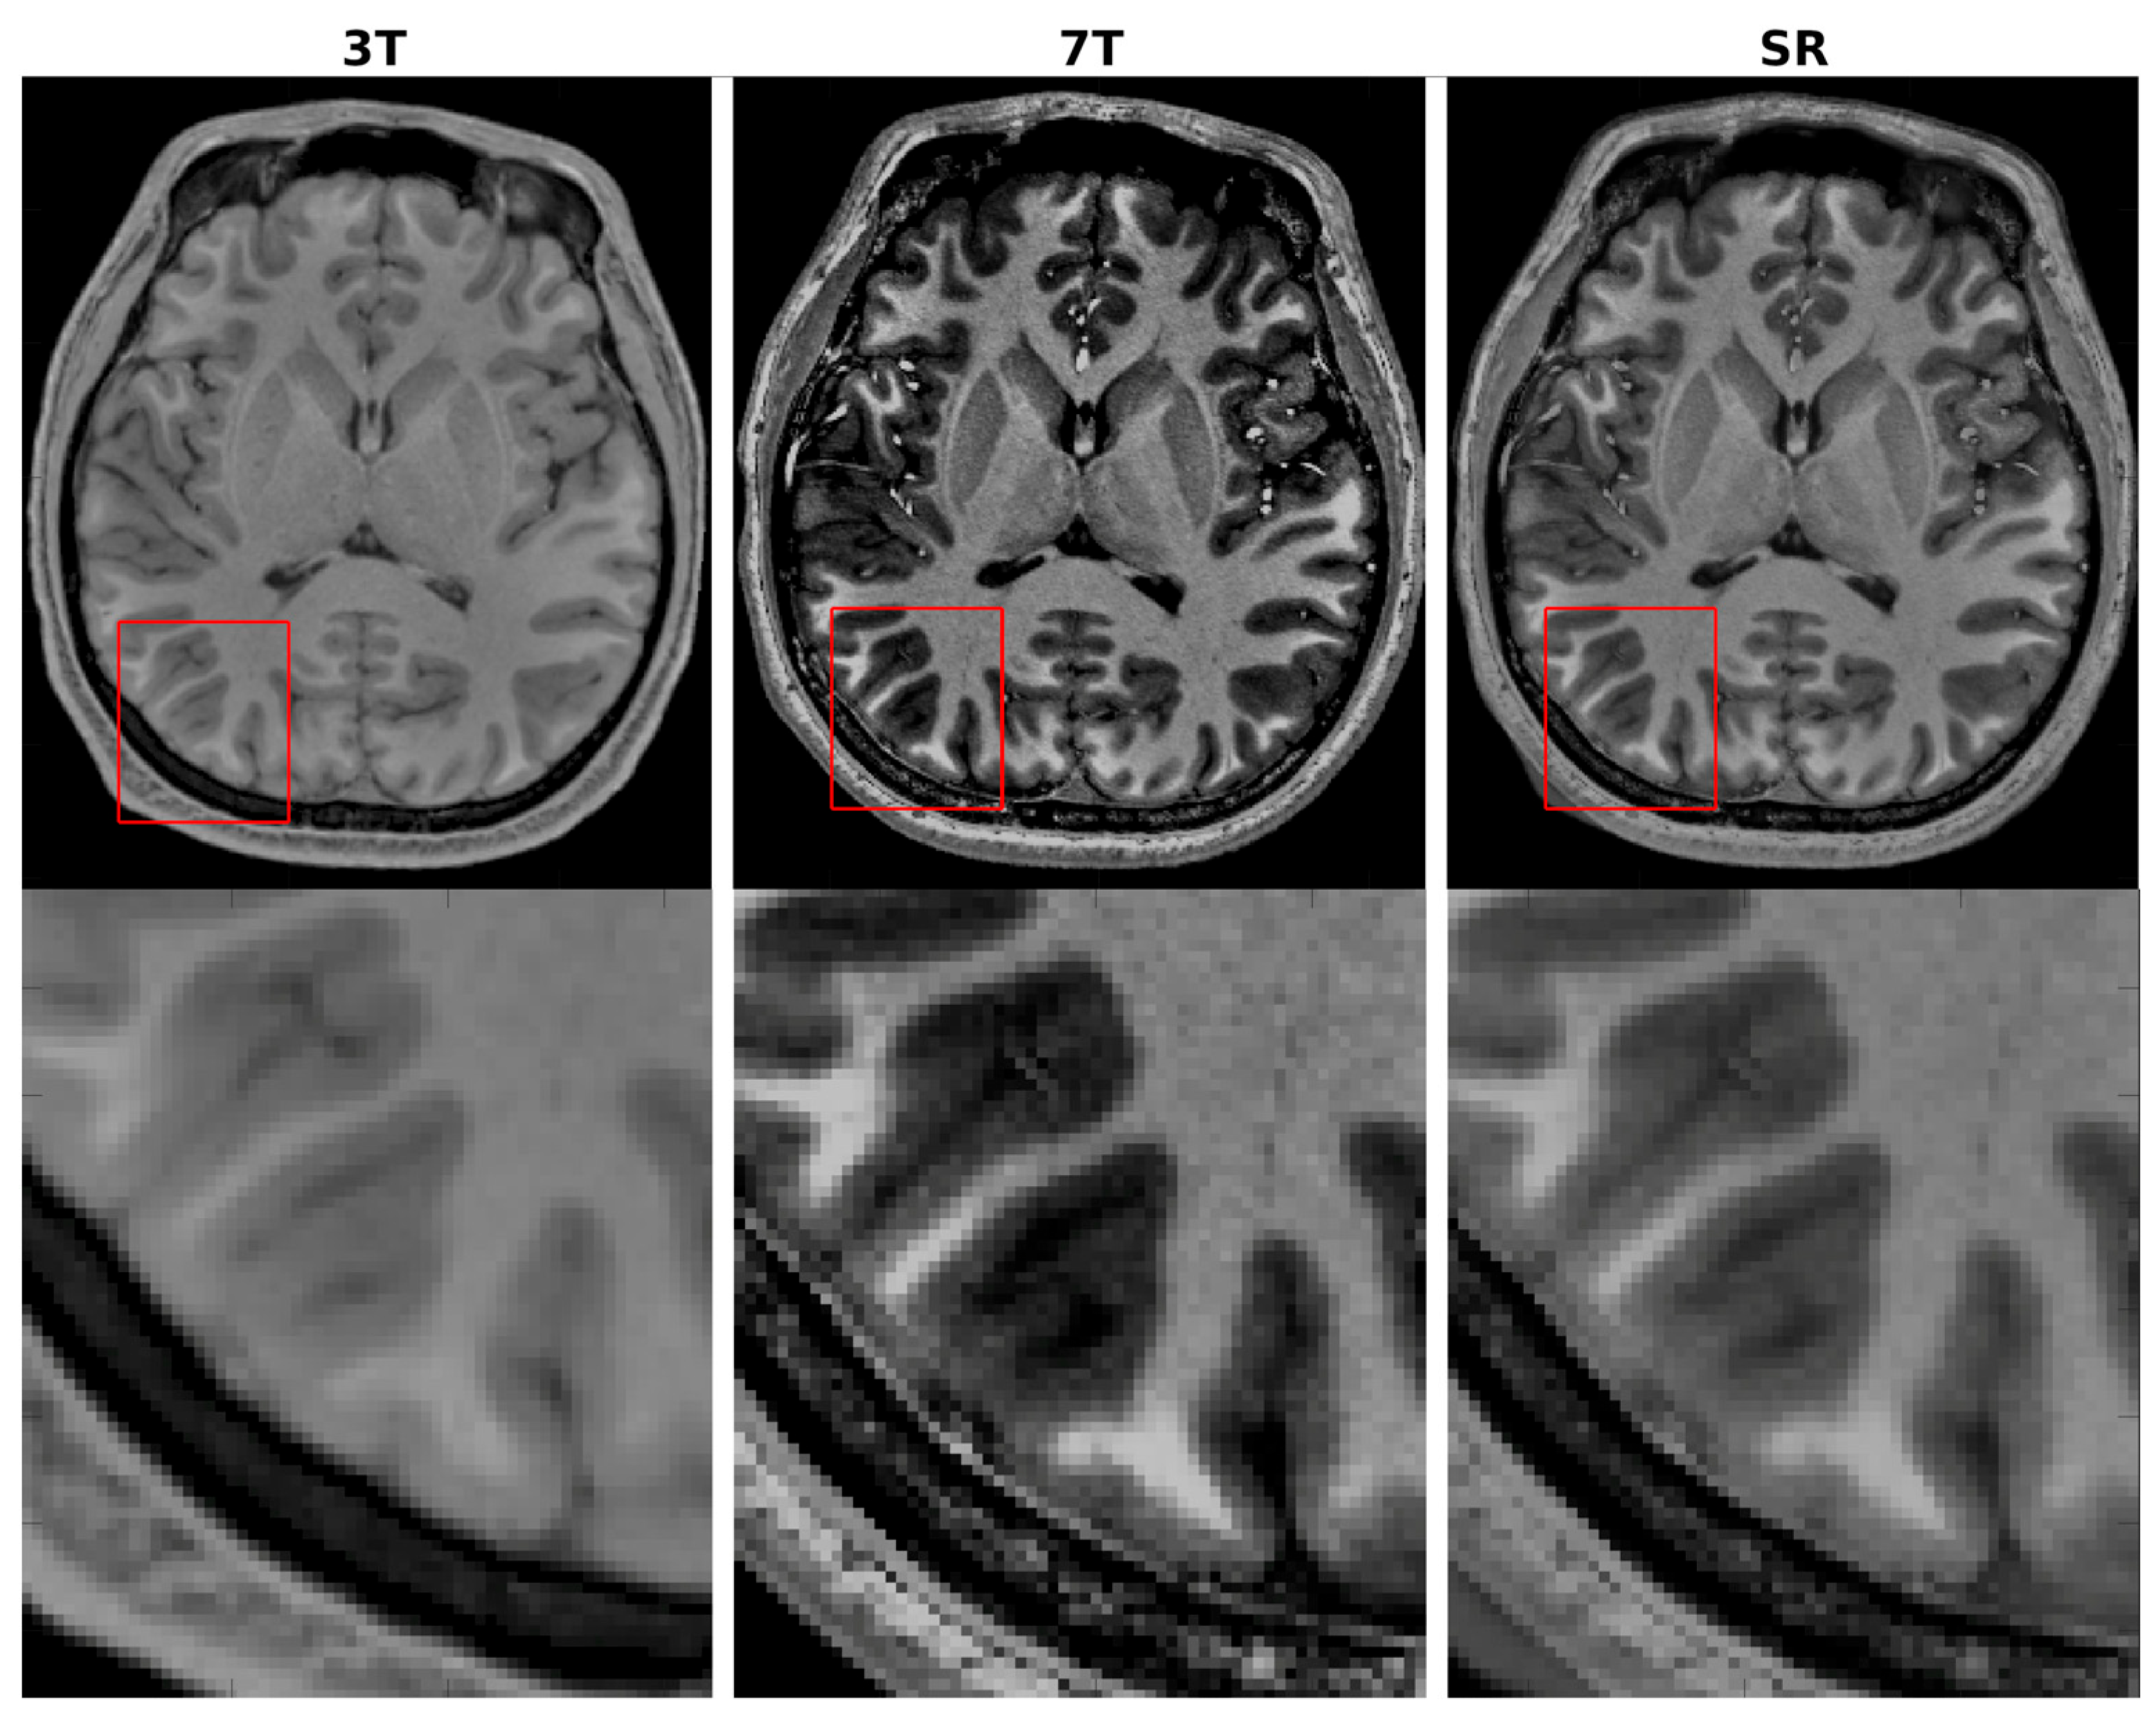

- With cross-field fine-tuning on only twenty subjects, CHARMS upgrades clinical 3T MRI to near-7T quality, yielding ~6 dB PSNR and 0.12 SSIM gains over native 3T scans across T1w/T2w contrasts.

4.3. Cross-Field Validation Using Paired 3T/7T Datasets